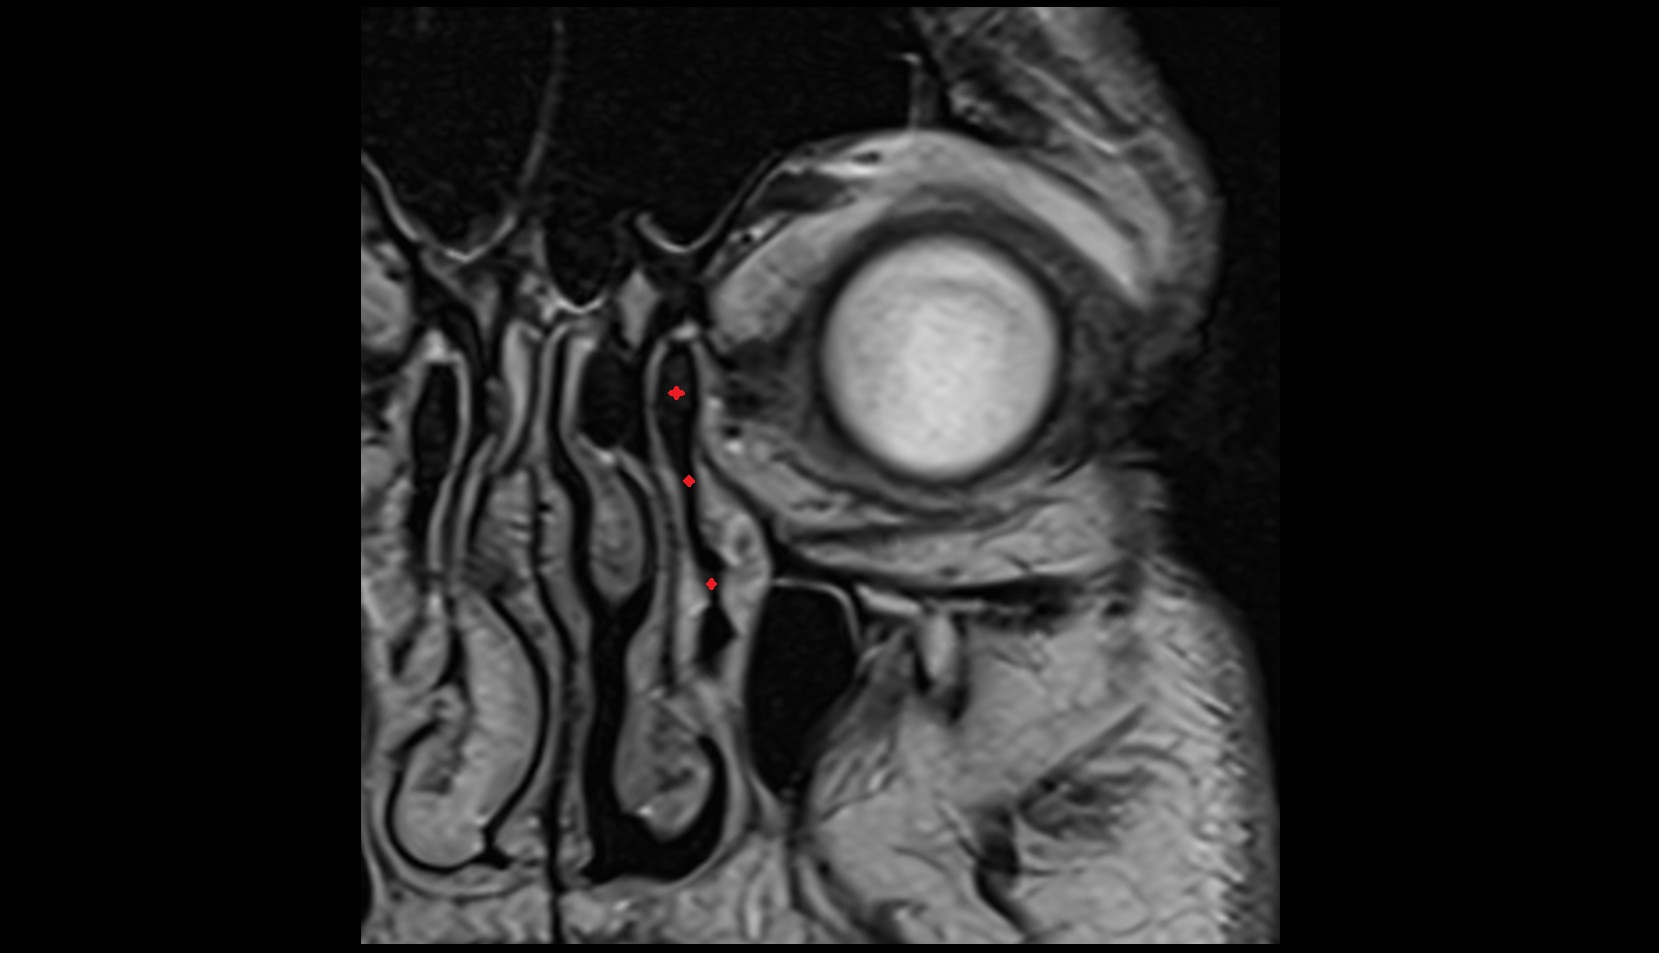

- Uterus

- Body of uterus

- Fundus of uterus

- Cervix of uterus

- Isthmus of uterus

- Vagina

- Fornix of the vagina

- Endometrium of uterus

- Myometrium of uterus

- Perimetrium of uterus

- Junctional zone of uterus